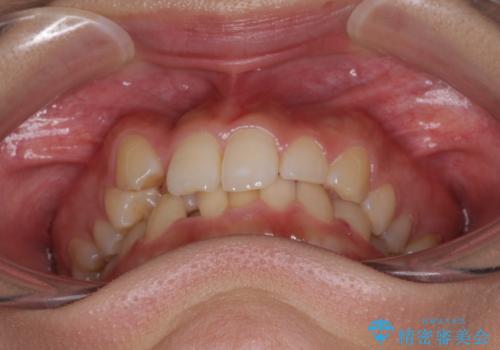

気になる八重歯を改善 補助装置併用のインビザライン治療

- 上顎の重なっている前歯を気にして来院された患者様です。

八重歯改善には抜歯が必要で、八重歯の移動量が多く、更には右側にずれている正中を改善する必要がありました。

インビザライン単体での治療は困難と判断し、補助装置により八重歯移動後にインビザラインを用いることとしました。